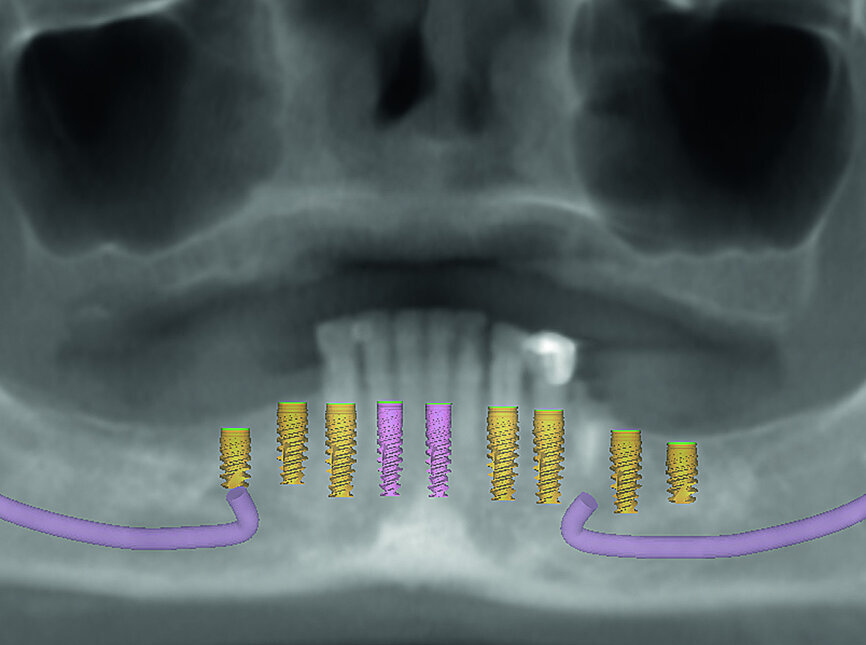

Fig. 3: Proposed treatment of maxillary arch.

Fig. 4: Proposed treatment of mandibular arch.

Fig. 5: Dentofacial analysis of proposed implants in maxillary arch.

Fig. 6: Dentofacial analysis of proposed implants in mandibular arch.

The patient returned for the records appointment, where maxillary and mandibular impressions were taken so that immediate temporary dentures could be fabricated for delivery at the surgical appointment. CBCT scanning was performed using a CS 8100 3D scanner (Carestream Dental) to provide the information needed for virtual treatment planning. The 3-D data obtained from the CBCT scans was used to determine the ideal length, width and placement of the implants in the key positions of the patient’s edentulous arches, including the first molar, first premolar, canine and central incisor regions (Figs. 3–6). From the digital treatment plan created by 3D Diagnostix, bone-level surgical guides were produced for the maxilla and mandible (Figs. 7 & 8).